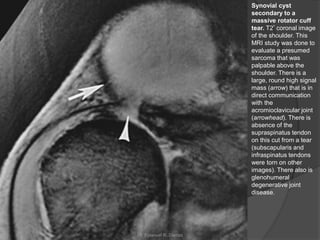

Synovial cyst

secondary to a

massive rotator cuff

tear. T2* coronal image

of the shoulder. This

MRI study was done to

evaluate a presumed

sarcoma that was

palpable above the

shoulder. There is a

large, round high signal

mass (arrow) that is in

direct communication

with the

acromioclavicular joint

(arrowhead). There is

absence of the

supraspinatus tendon

on this cut from a tear

(subscapularis and

infraspinatus tendons

were torn on other

images). There also is

glenohumeral

degenerative joint

disease.

• 76.

Alterações Diversas das Cápsulas,Bolsas e Tendões  Cistos Sinoviais:  Podem ocorrem em diferentes articulações (no ombro → tendem a ser grandes).  Causas: como conseqüência da AR, de lacerações maciças do manguito rotatório ou na vigência de uma artropatia neuropática.  Características de RM: ○ Demonstração da comunicação da massa (cisto) com a articulação do ombro e que tem baixa intensidade em T1 e alta intensidade em T2. ○ Com a injeção de contraste, apenas a periferia da massa sofre realce, demonstrando uma margem delgada sem paredes irregulares ou espessadas. Dr. Emanuel R. Dantas

• 77.

Synovial cyst secondary toa massive rotator cuff tear. T2* coronal image of the shoulder. This MRI study was done to evaluate a presumed sarcoma that was palpable above the shoulder. There is a large, round high signal mass (arrow) that is in direct communication with the acromioclavicular joint (arrowhead). There is absence of the supraspinatus tendon on this cut from a tear (subscapularis and infraspinatus tendons were torn on other images). There also is glenohumeral degenerative joint disease. Dr. Emanuel R. Dantas